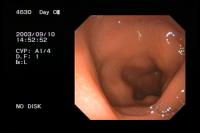

左の写真は、牛の発情期の子宮内の映像で、内視鏡を用いて撮影したものです。大学時代に撮影したもので、けっこう貴重かもしれません。